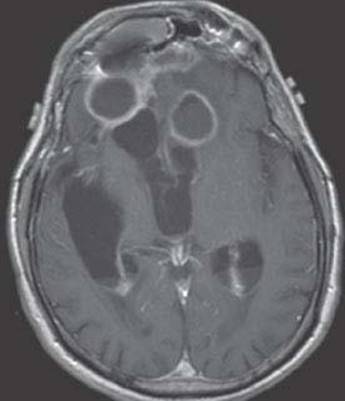

10. A 50-year-old man with long-standing AIDS, noncompliant with antiretroviral therapy, presented with a seizure, mild right-sided weakness, and confusion. Brain MRI showed at least three ring enhancing lesions with surrounding edema, the most prominent one in the left subcortical white matter. A brain biopsy was obtained, and the histopathologic specimen is shown in Figure 15.2. Which of the following is correct regarding the most likely organism causing this opportunistic infection?

FIGURE 15.2 Brain specimen. Courtesy of Dr. Richard A. Prayson. Shown also in color plates

This patient has toxoplasmosis of the CNS, which is caused by Toxoplasma gondii, an intracellular protozoan. The diagnosis in this case can be suspected based on the history and clinical findings and confirmed with the histopathologic findings showing a microglial nodule, in which an encysted bradyzoite can be seen surrounded by an inflammatory infiltrate.

Cerebral toxoplasmosis is the most frequent opportunistic infection in patients with AIDS. The organism is usually acquired earlier in life and remains dormant until the immune system declines and T. gondii becomes active. This occurs in advanced stages of immunodeficiency in the setting of CD4 counts of less than 100/μL.

Patients present with headaches, focal neurologic deficits, seizures, and altered mental status that can progress to coma. Brain MRI typically demonstrates multiple ring enhancing lesions with surrounding edema. Since these cases present with a mass lesion in the brain, the differential diagnoses include primary CNS lymphoma, tuberculomas, fungal masses, or bacterial abscesses. Definitive diagnosis is made with brain biopsy; however, this is not commonly performed, and patients are typically treated empirically.

Standard therapy is sulfadiazine plus pyrimethamine. Since both agents affect the folate metabolism pathways, folinic acid should be provided to avoid hematologic complications. An alternative therapy is clindamycin, especially in patients who are allergic to the sulfa components and cannot take sulfadiazine. Long-term suppressive therapy is needed to prevent relapses. Highly active antiretroviral therapy promotes immune reconstitution, and patients whose CD4 counts rise above 200/μL may not need further suppressive therapy. Trimethoprim-sulfamethoxazole is used for prophylaxis. Patients with HIV and CD4 counts of less than 200/μL with positive immunoglobulin G (IgG) antibodies to toxoplasma should be given prophylaxis.